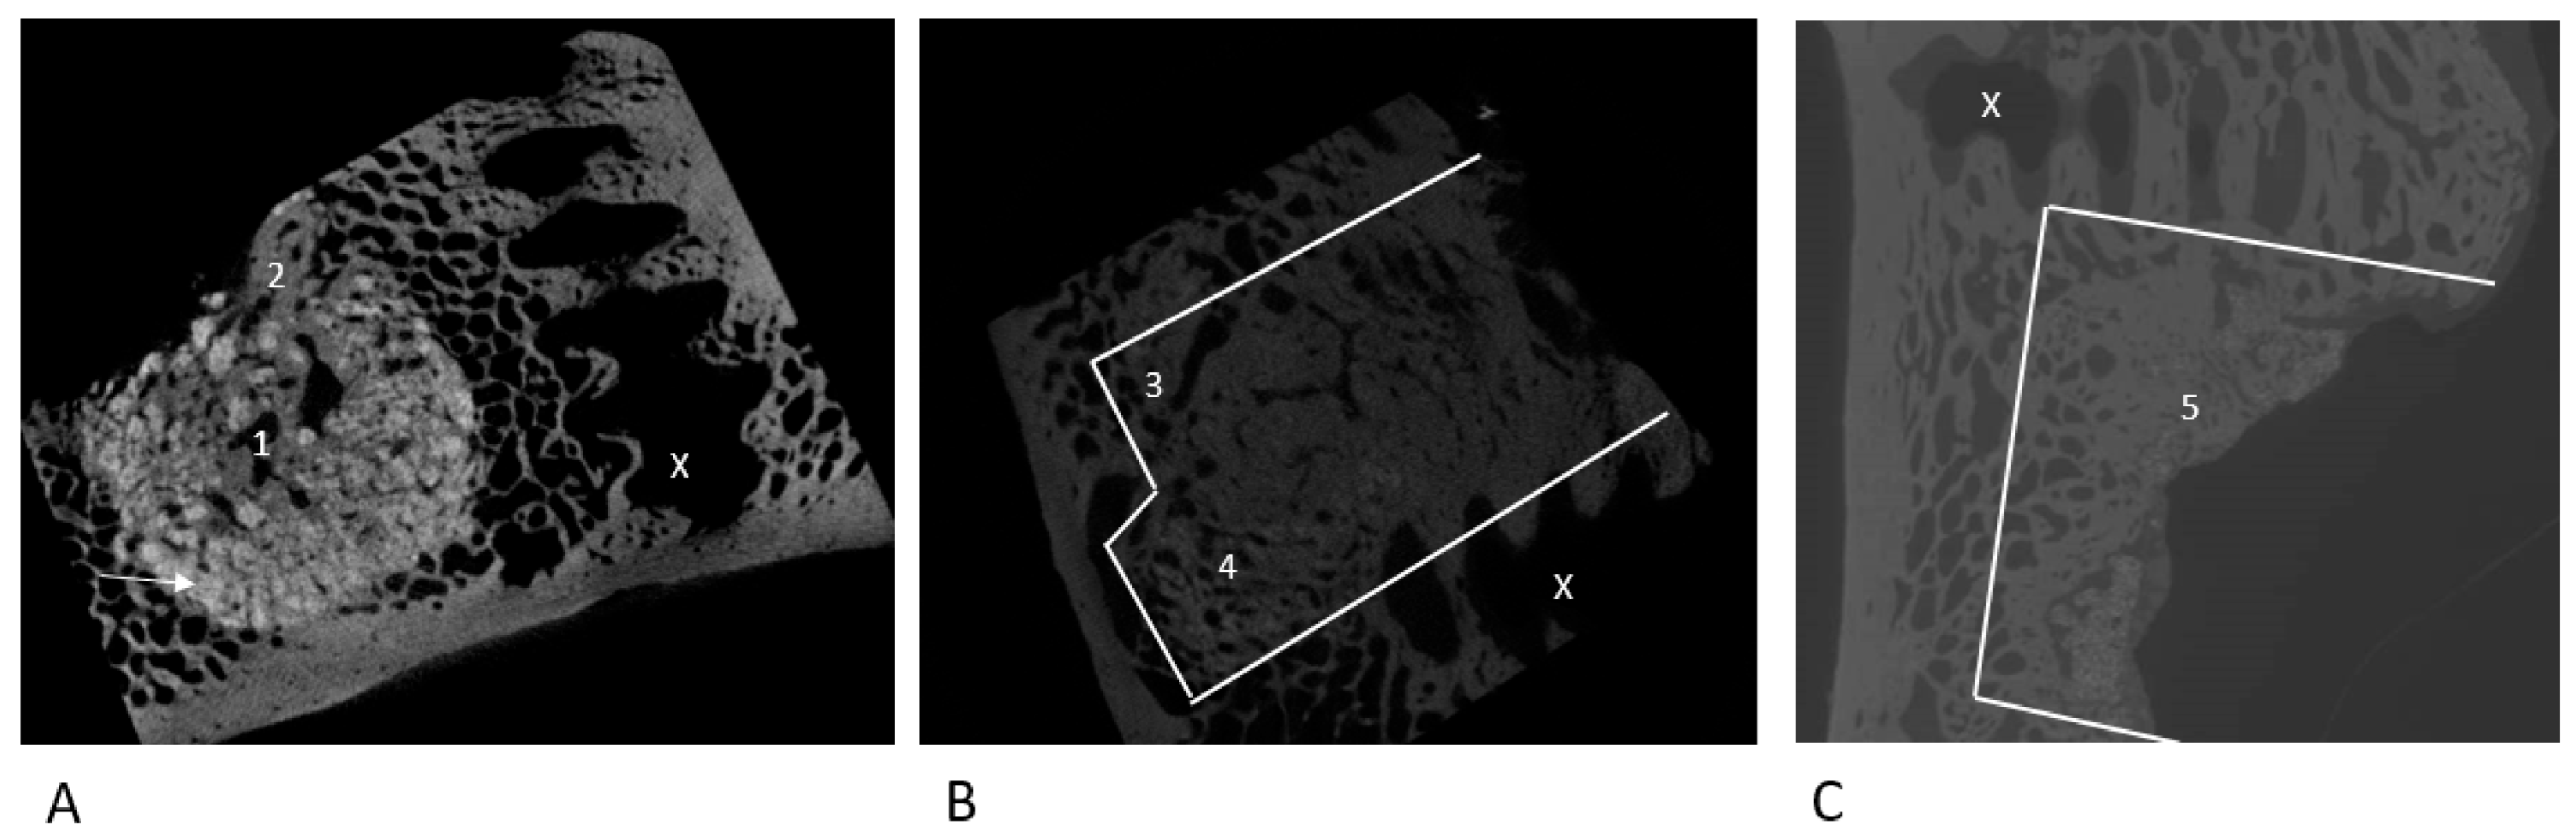

2.2. µ-CT Evaluation

3.2.1. NanoBone®

3.2.2. Autologous Sheep Cancellous Bone

3.2.3. Tutoplast® Cancellous Bone